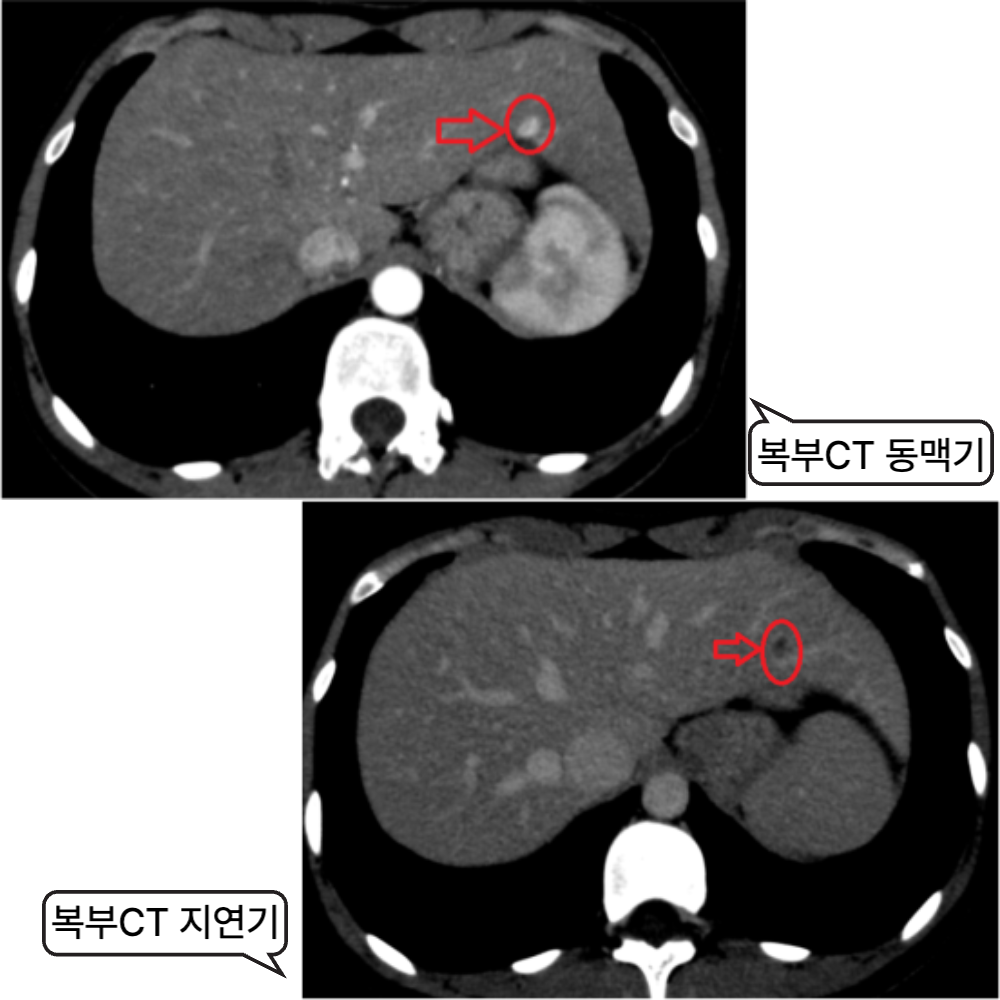

방치하면 치료 가능성이 줄고, 선택 가능한 치료 방식(수술, 고주파열치료 등)이 제한됩니다. 그래서 정기적인 검사, 특히 6개월마다 복부초음파와 혈액검사를 통한 간 기능/바이러스 수치 확인은 간의 건강을 지키는 효과적인 첫걸음입니다.

간암, 간염에 관련 사례를 확인하실 수 있습니다.